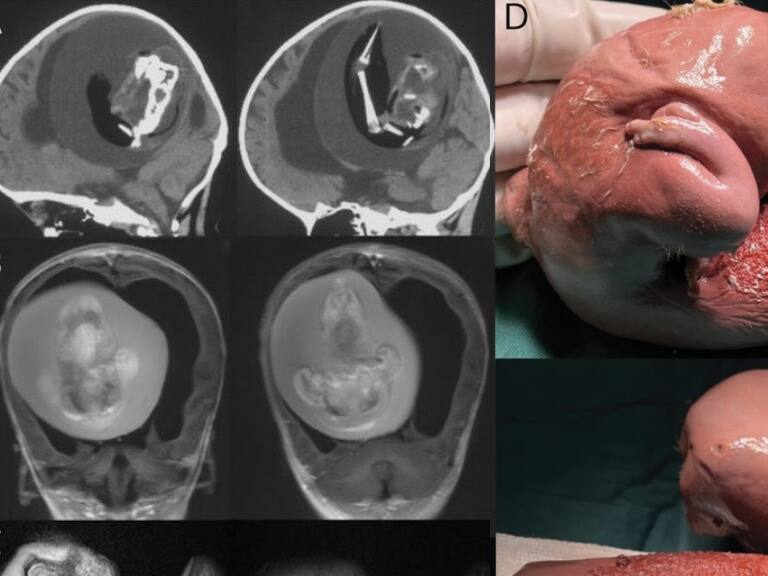

Los científicos de la Universidad de Fudan en Shangái, China, condujeron una investigación sobre una intervención quirúrgica en una niña, de 1 año, a la cual le sacaron el feto de su hermano gemelo. Anomalía que es conocida como «fetus in feto” (feto en feto) o «gemelo parásito”.

El reporte fue publicado en diciembre de 2022 en la revista Neurology, y corresponde a la masa extirpada desde la cabeza de la niña de un «gemelo diagnóstico monocriónico malformado”. En el útero, los dos fetos compartieron la misma placenta, pero tenían sacos amnióticos separados, según un artículo de Live Science.

Y en la intervención quirúrgica, se observó que el feto del «gemelo parásito» tuvo un desarrollo como: columna vertebral, dos huesos de la pierna y dedos en las extremidades superiores. Asimismo, se estableció que sufría de espalda bífida y que su crecimiento se dio por el suministro de sangre de su hermana.